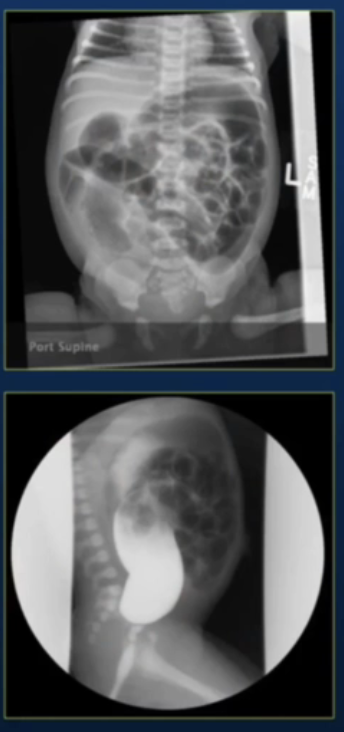

• Term baby girl presents on 2nd day of life with a distal bowel obstruction.

• Normal anus.

• Digital examination encounters resistance above the anal canal.

• Insertion of a 6-mm Hegar is followed by meconium passage.

• Plain film and enema are shown below.